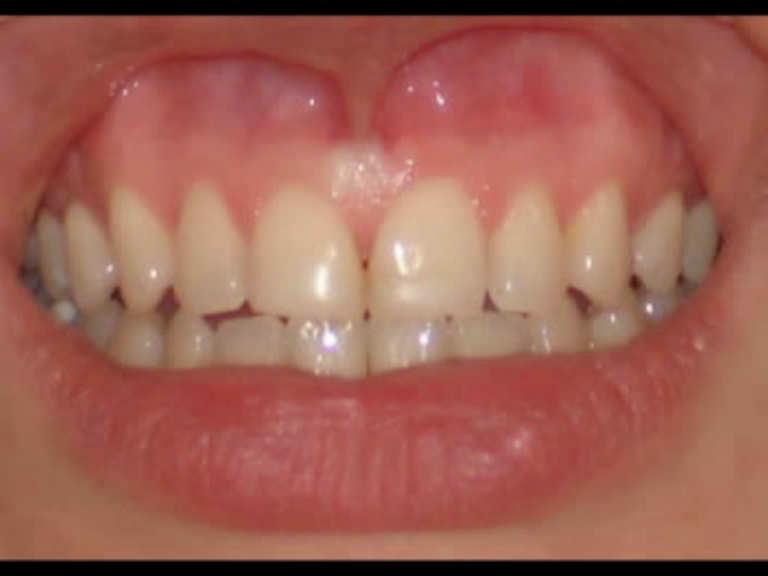

Diode Laser 810nm

Power: 2.5 Watt,

Pulsed 50 Hz ,Fibre 400 micron

Frenotomy-Tongue